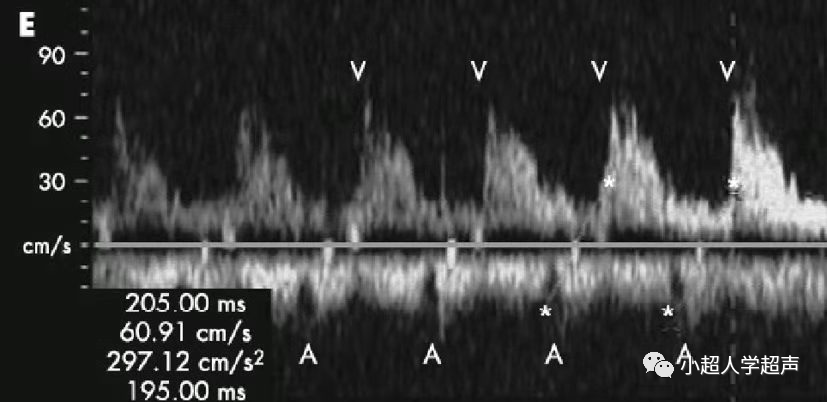

(2)二度房室传导阻滞

② 二度Ⅱ型房室传导阻滞是M型超或频谱多普勒A-V间距>150ms,规整,不伴有A-V间距进行性延长。房室传导周期性中断后,再重复。

等长-等长-等长-掉